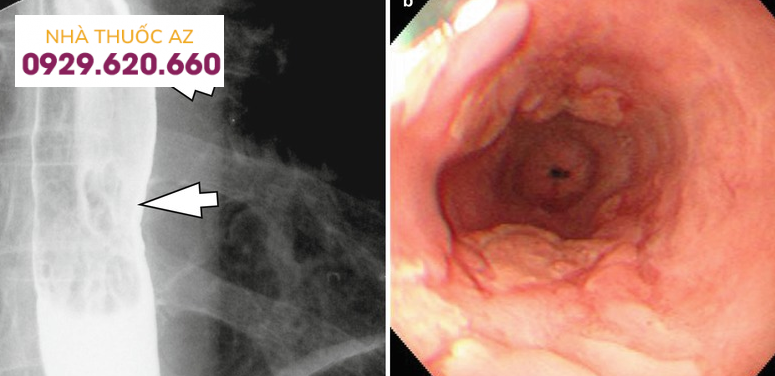

Trong số các phương pháp chẩn đoán hình ảnh, chụp X quang với thuốc cản quang Baryt thực quản là kĩ thuật được sử dụng phổ biến hơn cả, đặc biệt khi bệnh nhân có các triệu chứng nuốt khó hoặc nghẹn. Hình ảnh thường gặp trên chụp Baryt của viêm thực quản do bạch cầu ái toan là các vòng hoặc hẹp thực quản, tuy nhiên khi so sánh với nội soi, kỹ thuật này không thể đánh giá được các tổn thương ở niêm mạc thực quản.

Đối với hẹp thực quản, theo một nghiên cứu được thực hiện trên bệnh nhân thực quản do bạch cầu ái toan, tỉ lệ phát hiện được hẹp bằng chụp Baryt lên đến 71% trong đó chủ yếu là hẹp ở đoạn dưới thực quản. Một nghiên cứu khác ghi nhận đoạn hẹp chủ yếu nằm ở phía trên hoặc thực quản đoạn ngực.

Đường kính của đoạn hẹp trung bình khoảng 1cm và vị trí hẹp ở phía đoạn thực quản trên/giữa có xu hướng dài hơn so với đoạn dưới. Tùy vị trí đoạn hẹp trên chụp Baryt vẫn cần cân nhắc đến các chẩn đoán phân biệt khác. Các nguyên nhân khác gây hẹp ở đoạn thực quản trên hoặc giữa bao gồm thực quản Barrett, xạ trị vùng trung thất, sử dụng một số loại thuốc như NSAID, quinidine, trong khi hẹp ở đoạn dưới thực quản có thể do viêmthực quản trào ngược. Cần chú ý những bệnh nhân có hình ảnh hẹp thực quản trên chụp Baryt thường có triệu chứng nuốt khó và đây chỉ là một dấu hiệu gợi ý, cần kết hợp nhiều yếu tố liên quan đến bệnh sử, triệu chứng lâm sàng, hình ảnh nội soi và mô bệnh học.Vòng thực quản cũng là hình ảnh hay gặp với nhiều thuật ngữ được sử dụng như “khí quản hóa thực quản” hay “thực quản dạng vòng”. Vị trí và sự phân bố của các vòng thực quản rất khác nhau trên nội soi, có thể ở các đoạn của thực quản hoặc phân bổ lan tỏa nhiều chỗ. Đôi khi những vòng này có thể gây hẹp khiến dây sợi khó đưa qua được. Trên chụp Baryt, các vòng này thường nhiều, hay xuất hiện gần nhau, có dạng đồng tâm dọc theo lòng thực quản.

Mặc dù viêm thực quản do bạch cầu ái toan có một số hình ảnh đặc trưng, tuy nhiên cần chẩn đoán phân biệt với các hình ảnh viêm hẹp của thực quản Barrett, xạ trị vùng trung thất, sử dụng một số loại thuốc như NSAID, quinidine, và cần phải nội soi, sinh thiết làm mô bệnh học mới có thể xác định chẩn đoán.